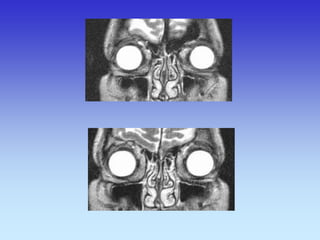

Upala sinusa

CT SINUSA

MMAKSILARNI SINUSI

ETMOIDINI SINUS